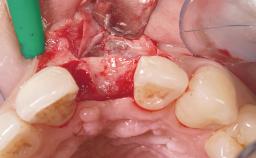

Early Placement of an Implant in a Maxillary Right Central Incisor Site

This 41-year-old female patient was referred to the clinic for the replacement of the right central incisor, since the tooth had developed a root fracture in the long axis that made extraction necessary. The healthy, non-smoking patient was first seen with the tooth still in place. A detailed Esthetic Risk Assessment was performed.The patient was worried about her dental esthetics and had high expectations for a successful treatment outcome from an esthetic point of view. The patient had a medium lip line that displayed parts of the gingiva in the anterior maxilla upon smile.

Bone Augmentation Horizontal|Simultaneous

Augmentation Materials Autogenous chips|Xenogenous|Membrane

Bone Volume Deficient horizontally, allowing simultaneous augumentation